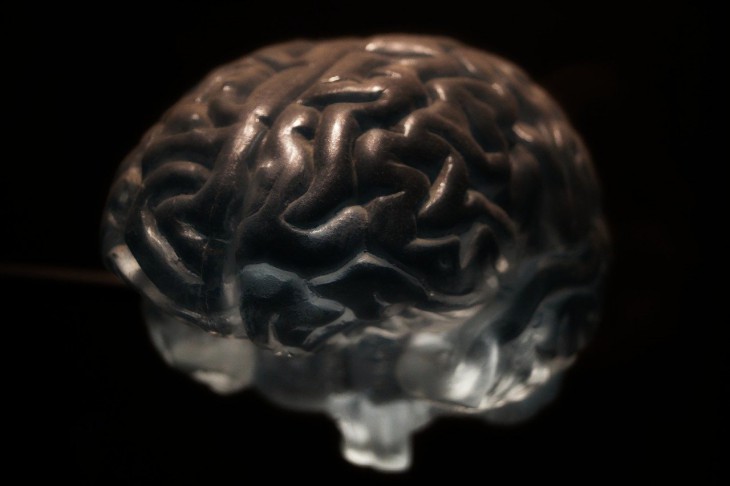

Оказалось, что вышеуказанное занятие способно спровоцировать образование необычных нейрофизиологических особенностей. Теперь их изучением занимаются американские ученые.

Благодаря исследованиям в данной области, они обнаружили некое общее сходство работы головного мозга.

За основу брались данные футболистов и боксеров, ушедших из жизни. Врачи проводили изучение анализов МРТ-снимков. Они демонстрировали зоны гиперинтенсивности белого вещества внутри головного мозга.

Как правило, они указывают на определенные заболевания, но часто проявляются у пожилых граждан или у пациентов с диагнозом гипертония. Оказалось, что деменция зачастую проявлялась перед смертью у игроков в американский футбол и боксеров.